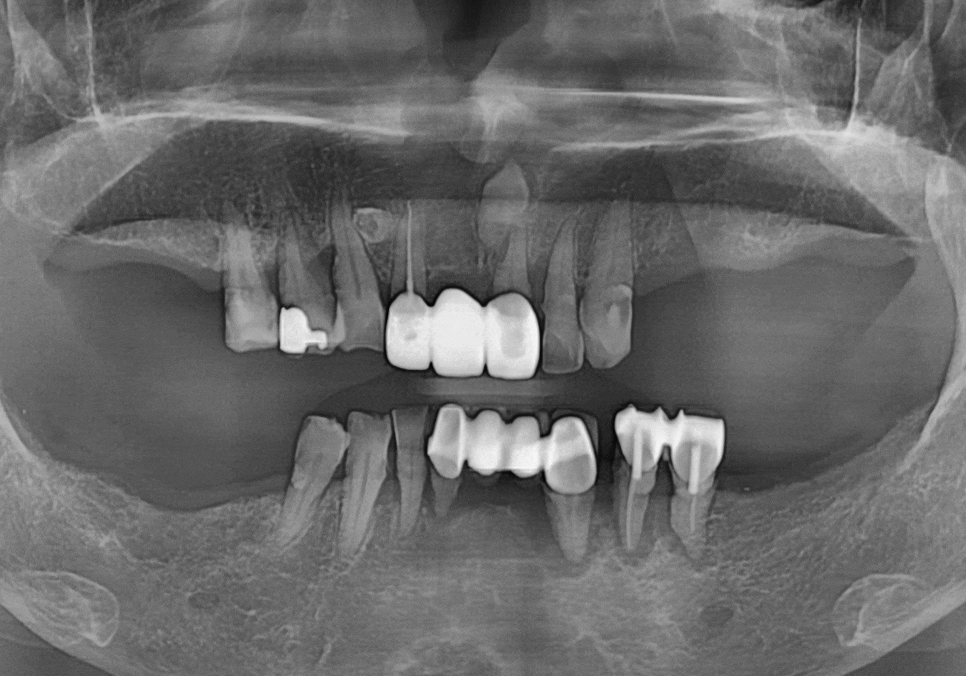

이분은 위아래 부분 틀니를

오랫동안 사용해오셨는데,

어느 순간부터 아래 틀니가 자꾸 들썩거리며

씹는 게 불편하다며 내원하셨어요.

검사 결과, 틀니를 지탱해주던

남은 치아 9개 중 무려 6개가

잇몸 질환으로 인해 심하게 흔들리고 있었습니다.

231023

지지대가 무너졌으니

틀니가 제 역할을 못 하는 것은 당연하겠죠~